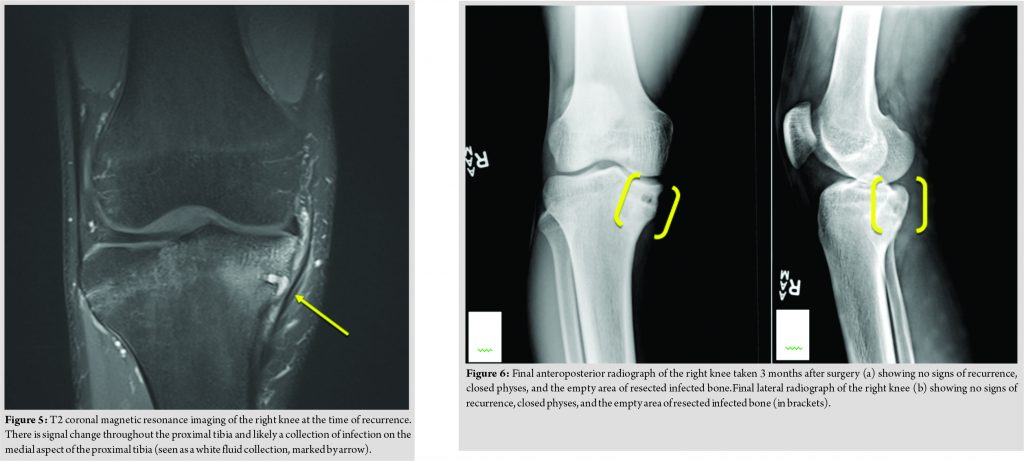

In April of 2017, approximately 1 year after completing therapy, he was seen in the infectious disease clinic again. At that time, the patient reported a 7-day history of pain, redness, and swelling along the inner aspect of the right upper leg below his knee overlying his prior surgical site. However, his father reported that he had complained of these findings for several months. A firm, tender erythematous mass over the medial aspect of the proximal tibia was noted on examination, underlying his surgical scar, although no drainage was present and the range of motion of his knee was normal. He had been a febrile and denied any recent trauma to the area. His ESR and CRP were normal at this time, as was his total leukocyte count and his differential leukocyte count. Plain radiographs demonstrated concern of recrudescent chronic osteomyelitis in the proximal tibia, with worsening sclerotic changes compared with his most recent radiograph (Fig. 3). A contrasted MRI demonstrated abnormal signal intensity in the proximal tibial metaphysis and epiphysis, with an abscess connected to a nidus of presumed chronic osteomyelitis througha fistula tract running inferior to the physis (Fig. 4 and 5). He was taken to the operating room shortly after this, where an abscess eroding through to the posterior aspect of the proximal tibia was noted. The superficial portion of the abscess was drained, with drilling through the affected bone into the posterior aspect of the tibia followed by curettage of the entire area. A cortical window was not created nor was periosteal elevation noted. His post-operative wound healing was uneventful. Operative cultures produced monomicrobial growth of P.aeruginosa, which, given the heavy growth in the primary streaks on the agar plate, was not felt to be a contaminant. This isolate demonstrated intermediate resistance to piperacillin-tazobactam (minimum inhibitory concentration (MIC)=32/4 mg/L), resistance to gentamicin (MIC>2 mg/L), aztreonam (MIC>16 mg/L), and ciprofloxacin (MIC>2 mg/L).The isolate was susceptible to meropenem (MIC of 1 mg/L), cefepime (MIC of 8 mg/L), ceftolozane and tazobactam (MIC=1.5 mg/L), and ceftazidime (MIC of 4 mg/L).Cefepime and ceftazidime MICs were confirmed with E-testing. Noimprovement was seen after 72 h of empiric cefazolin, but he did improve following transition to meropenem. Immunological evaluation revealed normal levels of natural killer cells, immunoglobulins (IgG, IgA, IgM, and IgE), tetanus, and pneumococcal antibodies. A lymphocyte subset panel was normal. He also demonstrated a normal lymphocyte proliferation response to phytohemagglutinin and pokeweed mitogen and a non-reactive serology to human immunodeficiency virus.Given the absence of an oral treatment option, he was treated initially with several days of cefepime, followed by 49 days of meropenem. He was then transitioned back to cefepime for 14 days followed by 56 days of ceftazidime. A contrasted MRI performed 7 weeks and plain radiographs performed 3 months into treatment demonstrated no recrudescence of disease (Fig. 6). He maintained normal inflammatory markers during treatment. At the end of 4 months of therapy, his physical examination was normal and his antibiotic therapy was discontinued. He denied any persistent symptomatology and was participating in soccer again without difficulty.